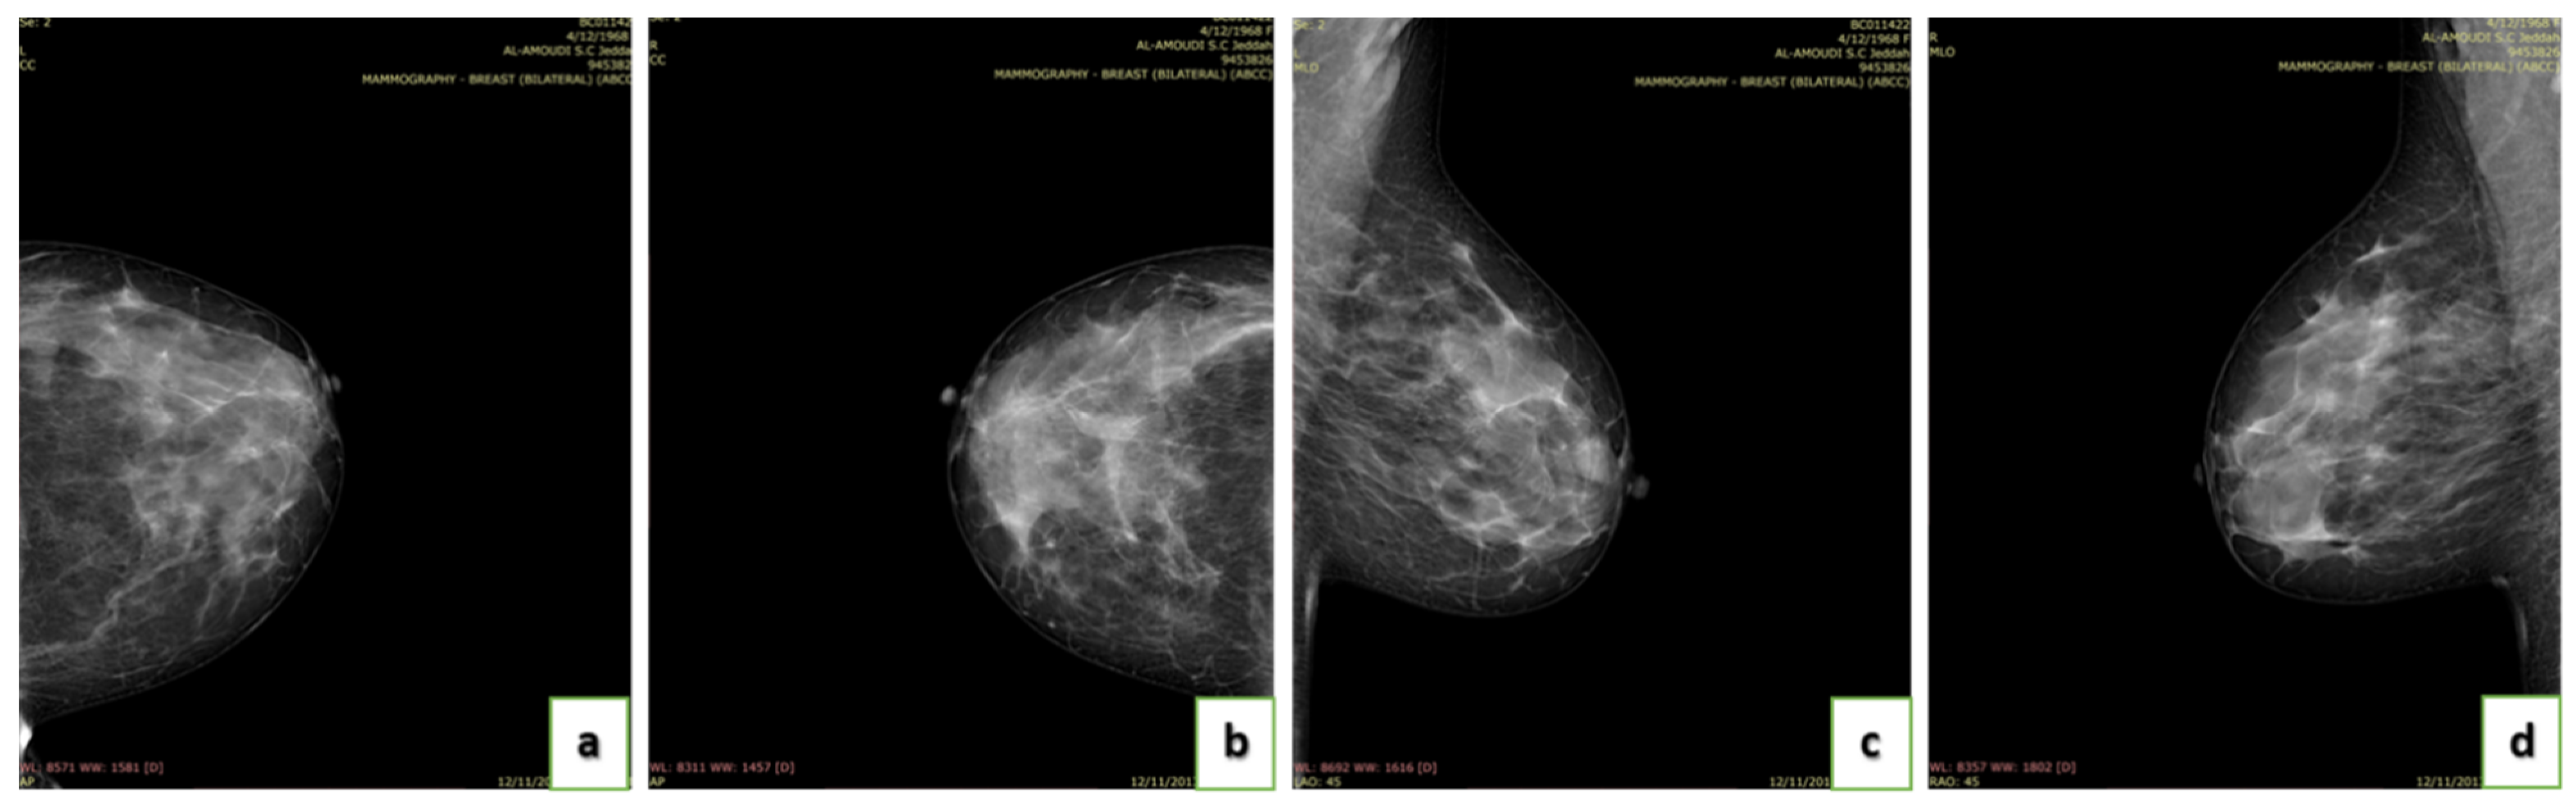

4.4. Breast Density

- A (0–25%): Almost entirely fatty indicates that the breasts are almost entirely composed of fat. One out of ten women has this result.

- B (25–50%): Scattered areas of fibroglandular density indicate some scattered areas of density, but most of the breast tissue is non-dense. Four out of ten women have this result.

- C (50–75%): Heterogeneously dense indicates that there are some areas of non-dense tissue but that most of the breast tissue is dense. Four out of ten women have this result.

- D (75–100%): Extremely dense indicates that nearly all breast tissue is dense. One out of each women has this result.